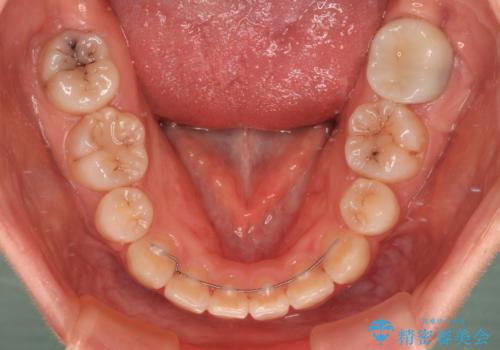

- メタルブラケット

- 2年4ヶ月

口元を積極的に引っ込めるために、上下左右の第一小臼歯を4本抜歯することとし、ワイヤー装置による矯正治療を行うこととしました。

上下前歯がくちばしのように突出していましたが、抜歯矯正により口元が引っ込み、唇が閉じやすくなり、鼻の下の膨れた感じも解消されました。